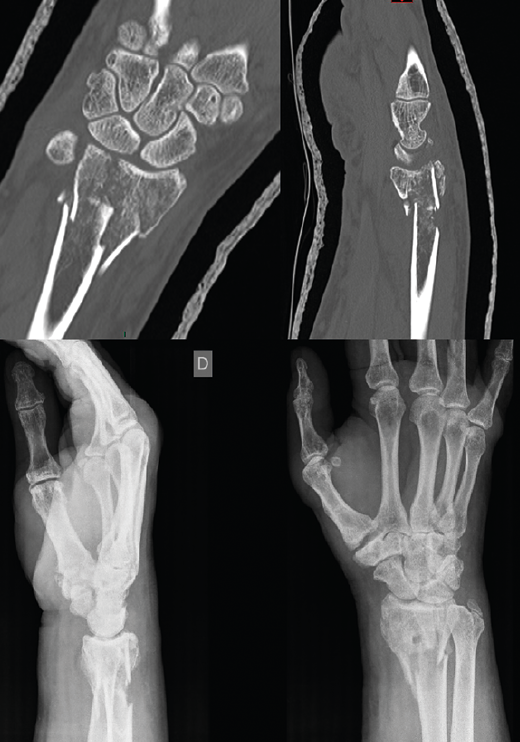

Figura 1. Radiografía simple y tomografía computarizada de fractura.

Se realiza radiografía simple y tomografía axial computarizada (TAC) (Figura 1). Se llevó a cabo la osteosíntesis con una placa volar Acu-Loc 2® distal ancha larga de Acumed y aporte de hueso de banco liofilizado en el foco metafisario. Se consiguió una reducción correcta (Figura 2). La herida evolucionó sin incidencias y se mantuvo al paciente 3 semanas inmovilizado con férula en U bloqueando la pronosupinación (sugar tongue). Posteriormente, inició una rehabilitación progresiva, con uso de ortesis rígida de descarga y controles clínicos y radiológicos cada 4-5 semanas.